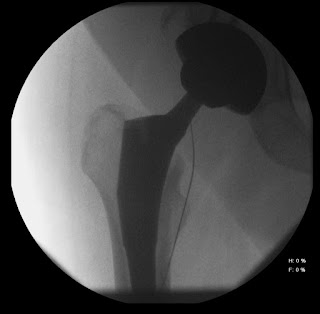

63 yo man with total hip arthroplasty, rule out septic arthritis. Large abdominal pannus significantly overlies hip joint; recent incision laterally. Used Morrison needle starting inferior and medial to joint, curving upward toward prosthetic joint.

Needle was extremely easy to use; stayed in place when stylet relaxed, removed. Procedure highly successful, avoided dangerous areas. Positioning took less than one minute.